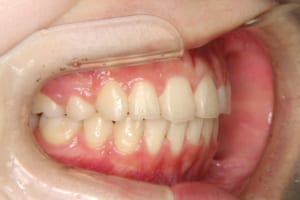

治療中